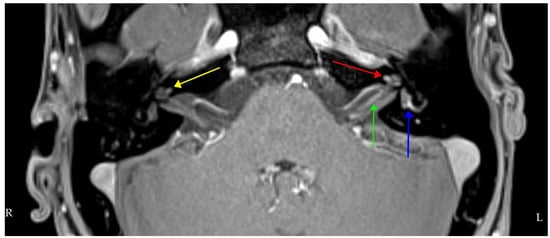

| Subtle left-beating nystagmus on left gaze only Bilateral catch up saccades in the horizontal plane on clinical head thrust testing (bilateral loss of vestibular function). Positive Romberg test Ataxic gait Normal positional (Dix-Hallpike) testing Summary: bilateral vestibular impairment, more marked on the right. Evidence of impaired dynamic and static balance. | Pure tone audiogram: bilateral moderate-to-severe SNHL, worse on the left Vestibular testing: Video head impulse test: bilateral low gain in both horizontal and vertical canals, with prominent covert and overt catch-up saccades on horizontal canal testing Impulsive rotational testing; minimal nystagmus generated bilaterally. Summary: bilateral audiovestibular dysfunction with hearing marginally worse on the left and vestibulopathy worse on the right. | Contrast-enhanced MRI four hours after IV Gadolinium: right cochlea enhancement, bilateral cochlear and vestibular hydrops and additional hydrops in the left lateral semicircular canal. |

| Clinical Examination | Audiovestibular Testing | Imaging |

| No spontaneous- or gaze-evoked nystagmus, normal saccades and normal smooth pursuit. Bilateral catch-up saccades in the horizontal plane, more obvious on the right on head thrust testing. Positive Romberg test Ataxic gait–marked Impaired tandem gait Positional (Dix-Hallpike) testing: normal Remaining neurological examination–normal apart from global peripheral hyporeflexia. Summary: bilateral vestibular impairment, more so on the left. Evidence of impaired dynamic and static balance. | Pure tone audiogram: bilateral profound SNHL Otoacoustic emissions: bilaterally absent Acoustic reflexes: bilaterally absent Vestibular testing–video head impulse test: bilateral low gain in both horizontal and vertical canals, more so on the right, with prominent covert catch-up saccades on horizontal canal testing on the right Summary: bilateral, largely symmetric, audiovestibular dysfunction. | Contrast-enhanced MRI IAMs and brain: bilateral cochlear enhancement and enhancement of the vestibule, lateral semicircular canal and cochlear nerve on the left. Pre-contrast T1 shortening suggestive of Cogan’s syndrome but differentials include inflammatory conditions (sarcoid, connective tissue disease, Behçet’s disease), infection and CSF-borne spread of neoplastic disease. CT temporal bones: nil significant findings |